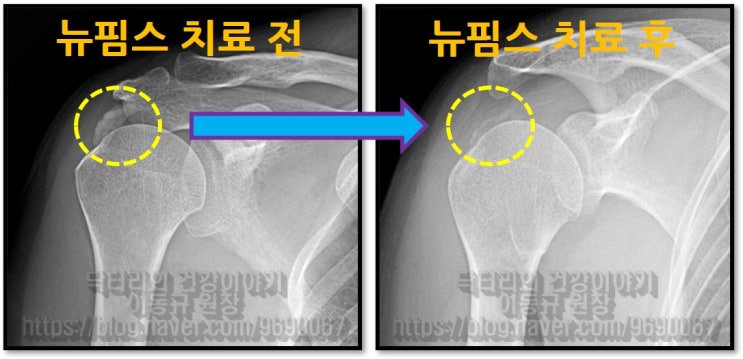

58세 여자 환자분으로 6개월 간 어깨 통증으로 고생을 하신 분입니다. 타병원에서 수차례 주사치료를 받았지만 증상의 호전이 없고 통증이 더 심해지고 가동범위 제한까지 오셨던 분이었습니다. 타병원에서는 수술적 치료를 권유받으셨다고 합니다. 석회성 건염 진단을 받으신 상태로 X-ray 를 확인해 보겠습니다.

이렇게 석회를 분쇄해서 흡입을 하게 되고 뉴핌스치료(석회분쇄흡입술) 후 찍은 X-ray를 보면

시술 후 통증이 확연하게 감소 되었고 환자는 아주 만족해 하셨습니다. 아직 남아있는 석회에 대해서는 추가적인 충격파 치료를 통해 치료를 하면 됩니다. 어깨 석회성 건염은 수술 없이 나을 수 있는 질환입니다. 물론 회전근개 파열이 동반되어 있다면 파열의 양상에 따라서는 다르겠지만 수술이 필요할 수도 있습니다. 하지만 석회성 건염만 있다면 수술을 필요치 않다고 생각합니다.